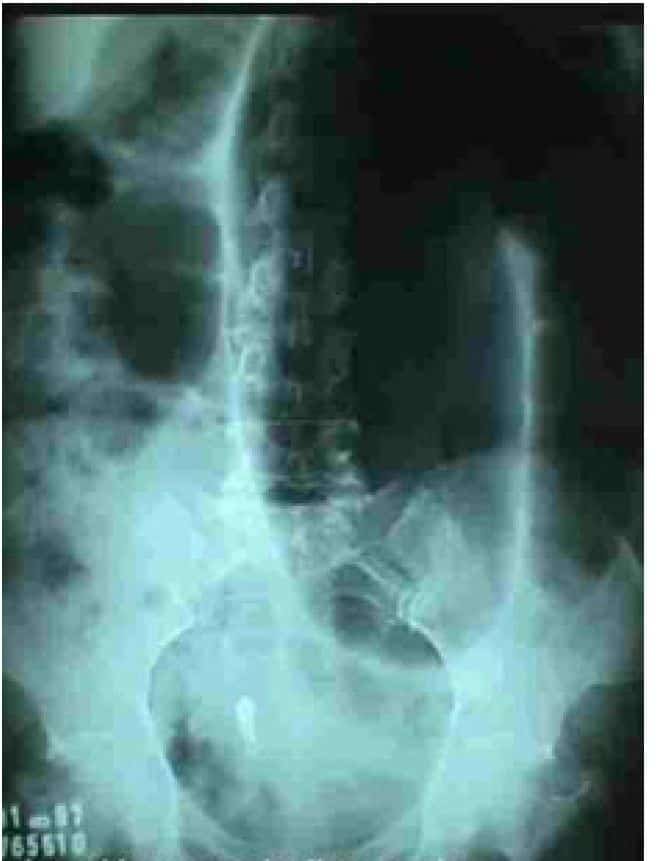

Patologías. Enema Opaco III

Tercera parte de patologías diagnosticadas por medio de enema opaco:

Tumor maligno recto – sigmoide